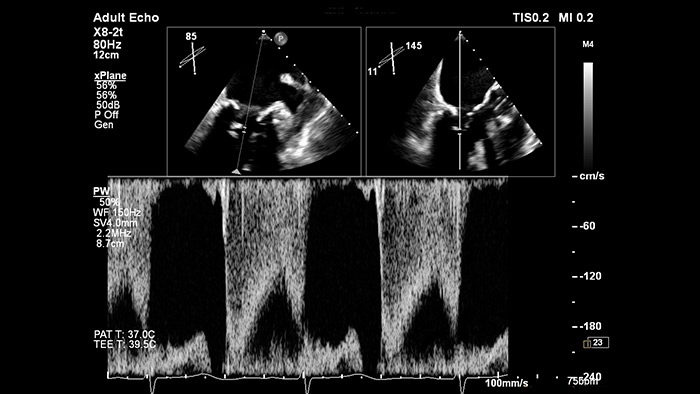

EPIQ CVx – xPlane Doppler

Zuverlässigere Platzierung von Doppler-Gates bei der Beurteilung des kardialen Blutflusses mit xPlane Doppler